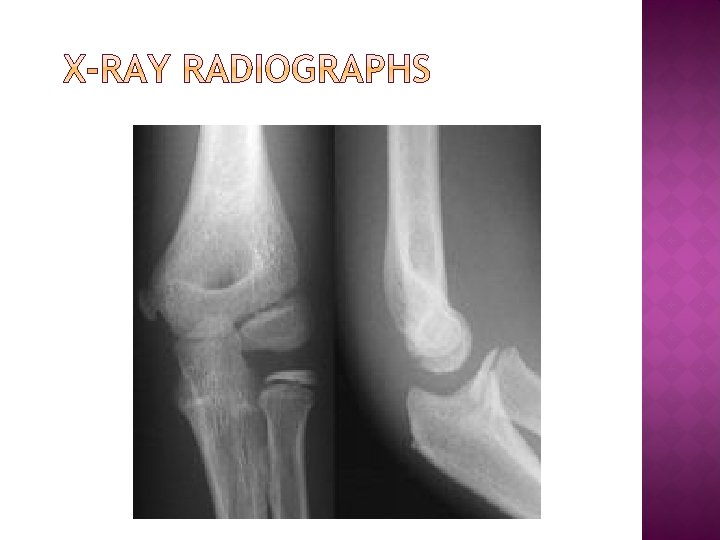

� Radiography is the use of ionizing electromagnetic radiation such as X-rays to view objects. Although not technically radiographic techniques, imaging modalities such as PET and MRI are sometimes grouped in radiography because the radiology department of hospitals handle all forms of imaging.

� Radiography started in 1895 with the discovery of X-rays , a type of electromagnetic radiation. Soon these found various applications, from helping to find shoes that fit, to the more lasting medical uses.

� X-rays were put to diagnostic use very early, before the dangers of ionizing radiation were discovered. The medical specialty of radiology grew up around the new technology, and new diagnostic tests involving X-rays were developed, it was natural for the radiographers to be trained and adopt this new technology. This happened first with fluoroscopy, computed (1960 s), and mammography � tomography Ultrasound (1970 s) and magnetic resonance imaging (1980 s) was added to the list of skills used by radiographers because they are also medical imaging, but these disciplines do not use ionizing radiation or X-rays.

� Diagnostic radiography involves the use of both ionizing radiation and non-ionizing radiation to create images for medical diagnoses. The predominant test is still the Xray. X-rays are the second most commonly used medical tests, after laboratory tests. This application is known as diagnostic radiography.

� Since the body is made up of various substances with differing densities, X-rays can be used to reveal the internal structure of the body on film by highlighting these differences using attenuation, or the absorption of X-ray photons by the denser substances (like calcium-rich bones). Medical diagnostic radiography is undertaken by a specially trained professional called a diagnostic radiographer in the UK, or a radiologic technologist in the USA.